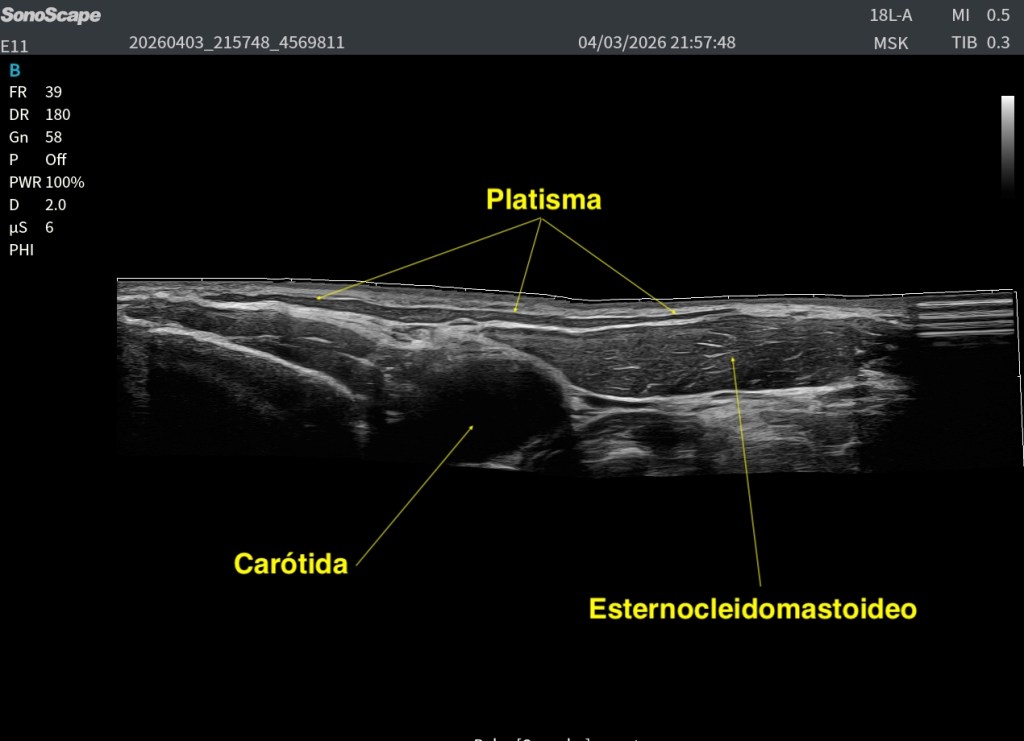

El Platisma es un músculo superficial, plano y muy fino, situado justo por debajo de la piel y del tejido celular subcutáneo, es el músculo más superficial del cuello.

Por encima de él solo encontramos piel y grasa, tejido celular subcutáneo en más o menos medida. Por debajo, ya entramos en estructuras más profundas del cuello anterior.

Te presento al músculo, en una imagen, como mejor puedo hacerlo, luego vamos a ir viendo sus relaciones anatómicas.

Ahí es donde empiezan a aparecer músculos como:

- El Esternocleidomastoideo ECM

- Los músculos infrahioideos (Omohioideo, Esternohioideo, Esternotiroideo)

- Glándula tiroidea

- Y más profundo aún, el paquete vascular con la carótida y la yugular

Por eso, el Platisma tiene una importancia clave: Marca el límite entre lo superficial y lo profundo en el cuello.